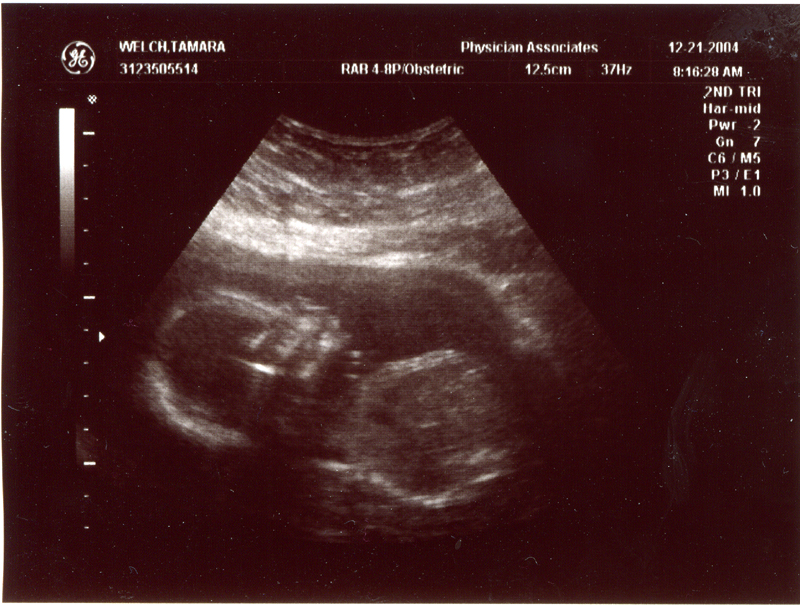

December 21, 2004 - We

had our second ultrasound and found out the sex of the baby. It's

a GIRL! We could see her moving around and see the heart beating.

We also heard the heartbeat during the doctor's visit. The heartbeat

is 150 bpm and the weight is 9 oz. Click on the images below to

see the pictures from the ultrasound. In the image titled "It's

a Girl" you can tell it's a girl because there is nothing

between the legs (the legs are in a "V" shape). We are

thrilled that everything is going well. We are planning to name

her Megan Storey Welch.